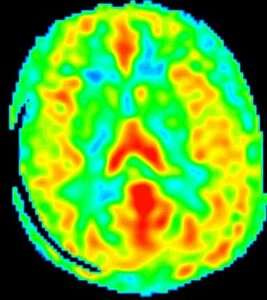

ASL(arterial spin labeling)法とは、脳の血流状態を評価する方法で、図のように描かれます。1) 2)

赤い部分が血流の多い場所を表します。

従来、脳血流の評価というと、放射線核種を用いる脳血流シンチグラフィー(SPECTやPETなど)や、造影剤を用いる検査でしたが、放射線の体内被曝や造影剤による身体的負荷の問題があり、大がかりな設備が必要でした。

MRI装置の高性能化、高磁場強度(3.0T)の装置の登場により、放射線被曝や侵襲のない検査が可能となりました。